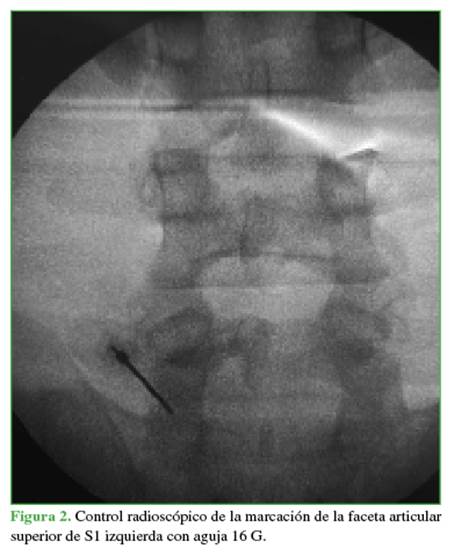

Bajo anestesia general, se ubica al paciente en decúbito ventral, y se procede al embrocado con clorhexidina y a la colocación de campos quirúrgicos para el abordaje posterior lumbar. Mediante radioscopia directa en posición de frente, se marca con una aguja 16 G en la punta de la faceta articular superior de S1 izquierda (Figura 2). Se realiza la incisión cutánea de 8 mm y la apertura de la fascia lumbar. A continuación, se desciende la cánula de trabajo junto con un endoscopio transforaminal Elliquence®, con óptica de 30º. Se procede al fresado lateral de la faceta de S1 con una fresa con adaptador para cirugía endoscópica. A medida que se genera el espacio en dirección ventral, se desciende la cánula de trabajo. Una vez localizada la cortical anterior de la faceta, se la reseca con una pinza Kerrison Rongeur de 3 mm. Luego, se efectúa un control radioscópico para asegurarse de la correcta dirección de trabajo (Figura 3).